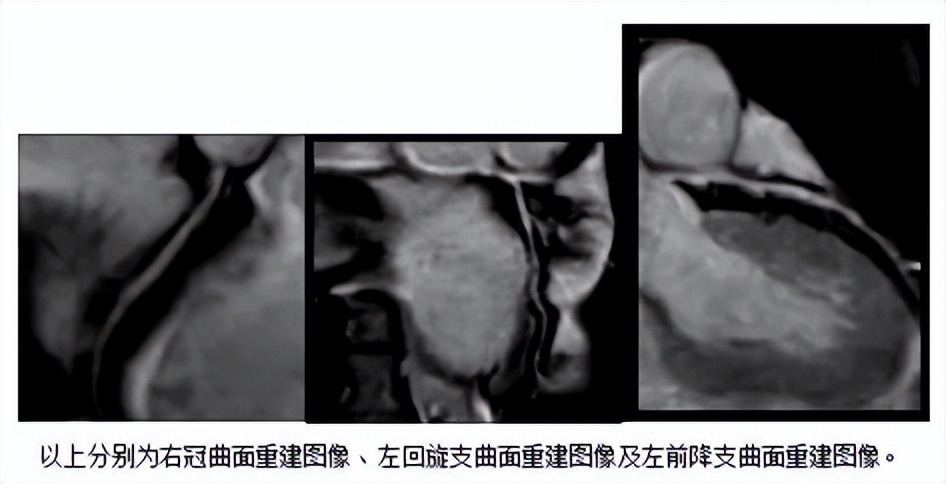

后经彭年春主任等专家多方评估后,认为患者可做不打药的冠脉磁共振血管造影检查。影像科收到医嘱后,由王正福技师使用飞利浦超高端磁共振Elition 3.0T对患者进行了检查,最终成功得到相关图像。后经分析发现,患者的左前降支轻度狭窄。接诊医生随后为其制定了详细的诊疗方案。